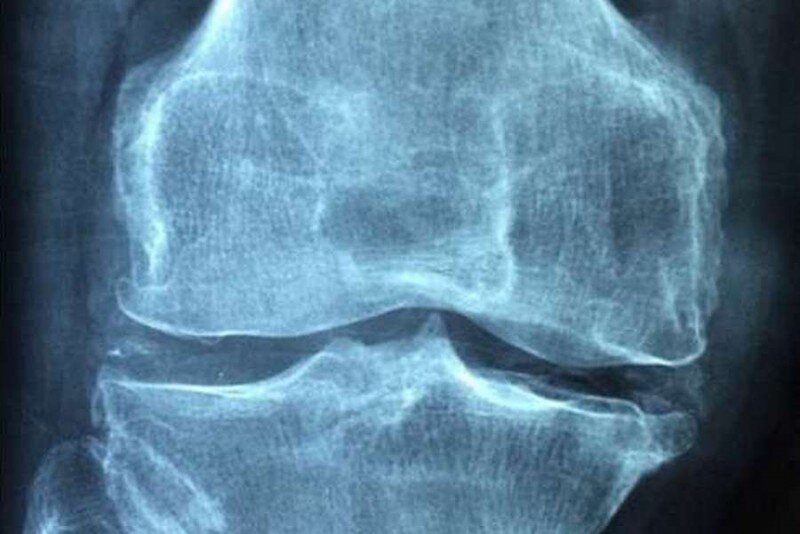

Так называемая «живая повязка», сделанная из стволовых клеток, могла бы революционизировать лечение серьезных травм колена. Она была успешно апробирована на людях учеными университетов Ливерпуль и Бристоль.

Более 90% травм происходят в одной из зон мениска из-за особенностей кровоснабжения которой его трудно восстановить. Многие предпочитают удаление поврежденной ткани полностью, рискуя получить остеоартрит в дальнейшей жизни.

«Повязка» из стволовых клеток была разработана Бристольским университетом и предназначена для того, чтобы разрыв мениска самовосстановился путем стимулирования роста клеток в пораженной ткани. Новый метод был апробирован на нескольких пациентах в возрасте от 18 до 45 лет, имевших травму менниска.